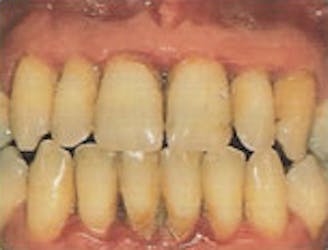

Periodontitis

- Gum boils or abscesses may develop

- Teeth look longer as gums begin to recede

- Front teeth may begin to drift, showing spaces

- Constant bad breath and bad taste

- Both horizontal and angular bone loss on x-ray

- Pockets between teeth and gums range from 4-6mm deep